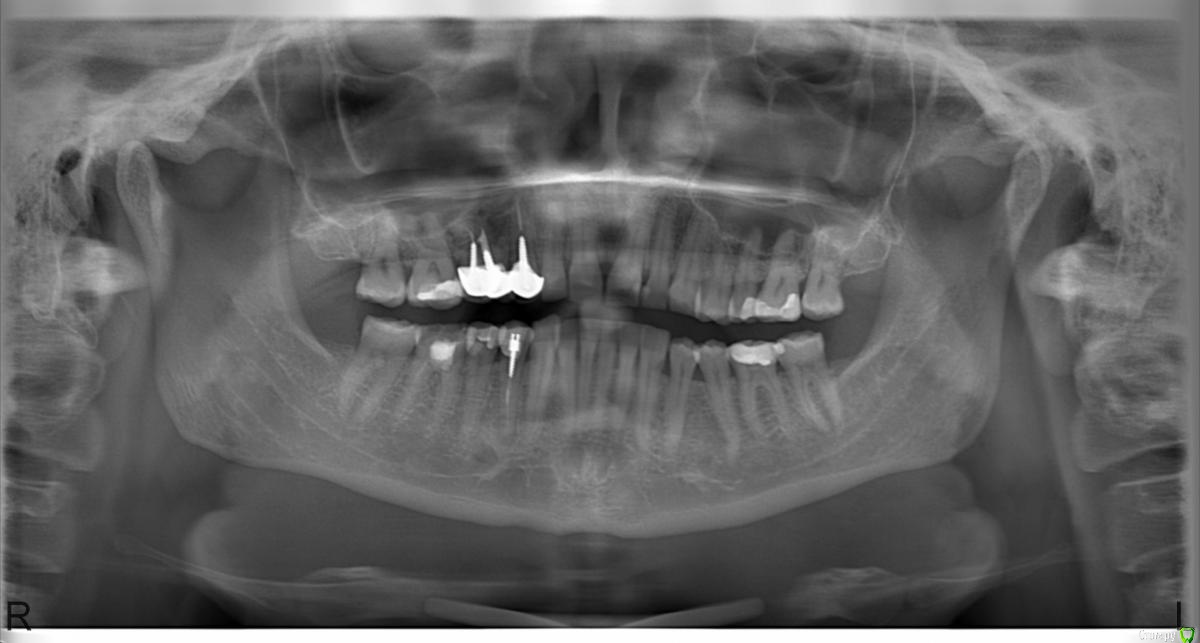

Lollipop Опубликовано 2 августа, 2015 Поделиться Опубликовано 2 августа, 2015 Уважаемые господа-хирурги!Большая просьба оценить результаты имплантации. По словам хирурга - все отлично, расстояние между коронками хорошее, с десневыми сосочками проблем быть не должно, по словам ортопеда - розовая керамика и отсутствие эстетики в связи с недостаточным горизонтальным расстоянием. В настоящий момент сосочки между формирователями абсолютно отсутствуют, десна имеет выгнутую кверху дугообразную форму. Кто прав - хирург или ортопед? Можно ли исправить ситуацию с десной подсадкой ССТ и какие перспективы у дальнейшего протезирования? Смущает так же близость верхушки имплантата и корня зуба 1.2.Заранее огромное спасибо!!!! Ссылка на комментарий

Aquarius Опубликовано 2 августа, 2015 Поделиться Опубликовано 2 августа, 2015 (изменено) Средний имплант, мягко говоря, здесь совсем не нужен) До корня двойки далеко, не волнуйтесь. Изменено 2 августа, 2015 пользователем Aquarius 2 Ссылка на комментарий

AlexanderGudkov Опубликовано 2 августа, 2015 Поделиться Опубликовано 2 августа, 2015 Перспективы протезирования - розовая керамика Ссылка на комментарий

Aquarius Опубликовано 2 августа, 2015 Поделиться Опубликовано 2 августа, 2015 Глушить имплант ( зашивать после выкручивания формирователя) и работать с мягкими тканями плюс временные коронки Ссылка на комментарий

Aquarius Опубликовано 2 августа, 2015 Поделиться Опубликовано 2 августа, 2015 Елена,в первую очередь-сделайте прицельные рентген-снимкм этих трех имплантов. можно и в нейтральной клинике. Во вторых,если есь возможность,сделайте томограмму . Простите за орфографию. Пишу с телефона. Ссылка на комментарий

Mane Опубликовано 2 августа, 2015 Поделиться Опубликовано 2 августа, 2015 Ситуация из простой перешла в очень сложную. Вам нужно заглушить или удалить средний имплантат. На оставшихся других провести пластику десны. Так как провал просто огромен, скорее всего 2 раза. Так же нужно восполнить убыль десны на зубе 1.2 (боковой резец). Иных вариантов нет. 2 Ссылка на комментарий